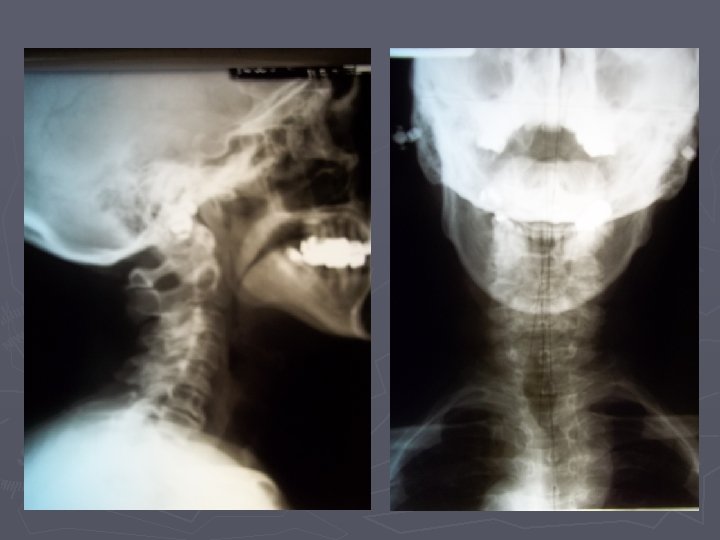

“However the glossopharyngeal nerve remains the neglected cranial nerve. This is because the nerve “However the glossopharyngeal nerve remains the neglected cranial nerve. This is because the nerve is small and lies deep within the neck, and surgeons often do not encounter the nerve even with deep dissections of the neck. The nerve is not commonly identified or visualised even when performing a major neck operation, for example a radical neck dissection. A more important reason is because the glossopharyngeal nerve supplies important structures in the head and neck region only in the company of another cranial nerve. It does not supply an important structure in isolation and has no monopoly in the innervation of any critical organ. Mother Nature had not entrusted the glossopharyngeal nerve an important vital function in the same way that she had given roles of importance to the other cranial nerves. Never less, Glossopharyngeal neuralgia can be life-threatening. ” Soh KB. The Glossopharyngeal Nerve, Glossopharyngeal Neuralgia and the Eagle’s Syndrome - Current Concepts and Management, Singapore Med J 1999; Vol 40(10)

Immediately after specific adjustments to C 5, C 2 and C 1, pain diminished Immediately after specific adjustments to C 5, C 2 and C 1, pain diminished from 10 to 1. Tremor and head tilt were eliminated. Eye clarity and facial color returned to normal. She could talk normally. Two days later pain was 0. Six weeks later she was completely free of seizure and pain medications. She has sold her home in North Dakota and moved to Grand Rapids, MI.